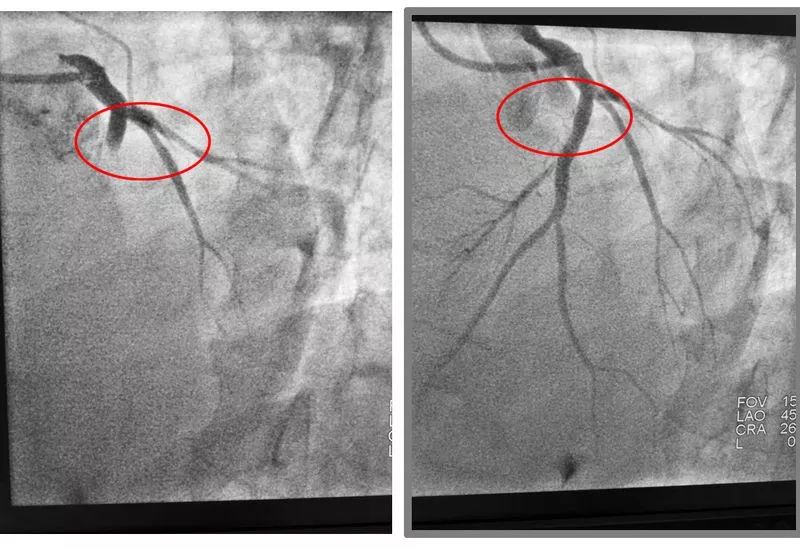

心內(nèi)科急診PCI手術(shù)中

冠脈造影顯示男子冠狀動脈左前降支近段100%閉塞,植入支架后恢復(fù)了血流。